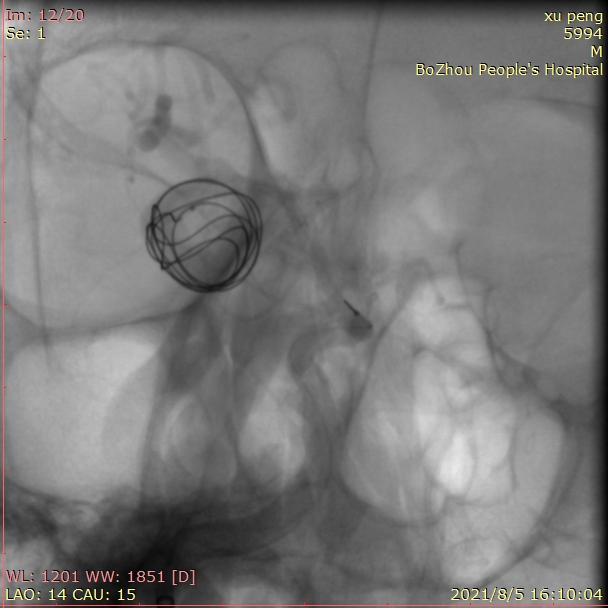

成篮圈的即刻造影和蒙片

依次填入14/30、13/30、11/30、10/20*2弹簧圈后,发现第一根微导管已经基本固定在瘤颈上方,而瘤体中心及下方仍显影明显。这时我们暂不撤回第一根微导管,然后将第二根SL-10微导管塑形后送入瘤内下方继续填圈。

用两根微导管依次缓慢、小心填入9/30,8/30,7/20,6/20,5/10,3/8等圈,即刻造影,动脉瘤不显影,最终达到完全栓塞。